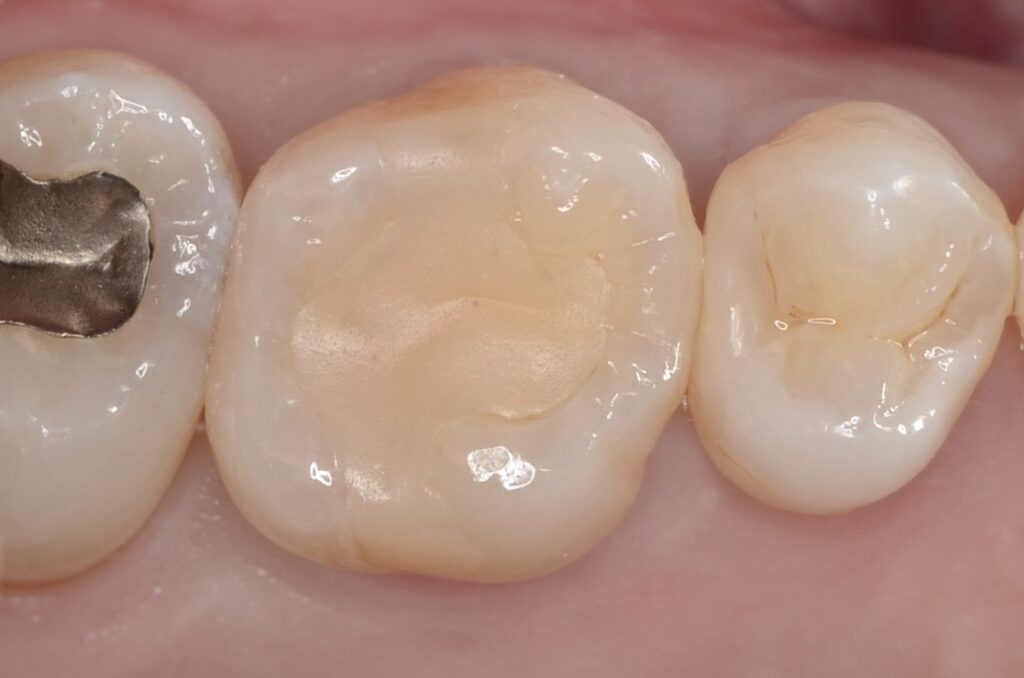

40代 虫歯治療 ダイレクトボンディング #52

Before

After

| 年齢 | 40代 | 治療方法 | ダイレクトボンディング |

|---|---|---|---|

| 性別 | 男性 | 通院回数 | 2回 |

| 主訴 | むし歯を治したい | 費用 | 115,500円(税込) |

| 治療のメリット | 歯を削る量を少なくできる・自然な見た目・境目がピッタリできる | ||

| 治療のデメリット | 大きい虫歯治療には適応できない場合がある | ||